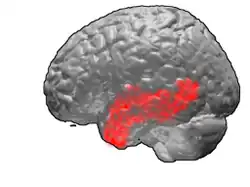

Brodmann area 21

Brodmann area 21, or BA21, is part of the temporal cortex in the human brain. The region encompasses most of the lateral temporal cortex and is also known as middle temporal area 21. In the human it corresponds approximately to the middle temporal gyrus.

BA21 is a subdivision of the cytoarchitecturally defined temporal region of the cerebral cortex. BA21 is superior to BA20 and inferior to BA40 and BA41. It is bounded rostrally by the temporopolar area 38 (H), ventrally by the inferior temporal area 20, caudally by the occipitotemporal area 37 (H), and dorsally by the superior temporal area 22 (Brodmann-1909).